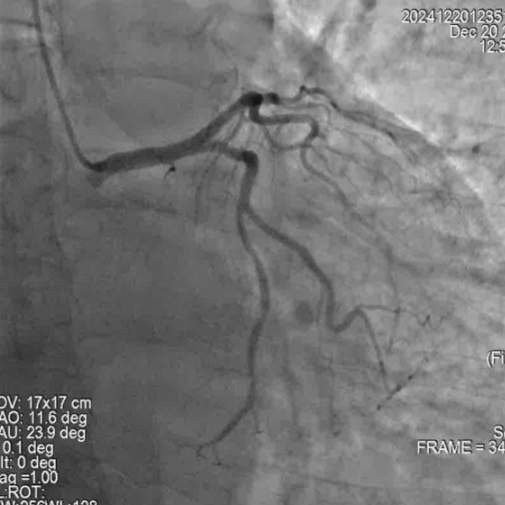

冠脉造影

手术过程